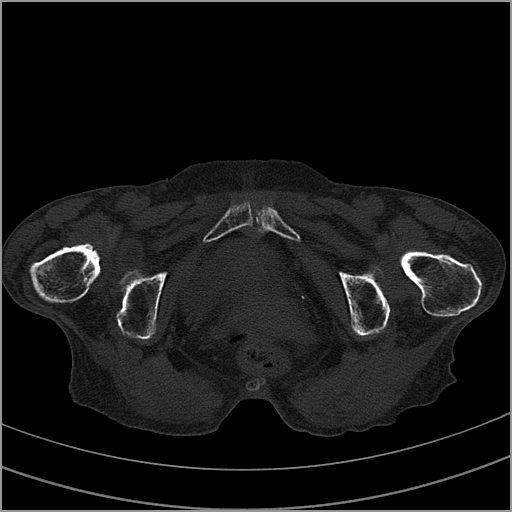

以下是引用老爱克斯新网客在2009-2-3 19:42:00的发言:[br]右侧髋臼及右侧股骨头可见明显骨质破坏,以溶骨性破坏为主,无明显硬化,髋关节间隙变窄,周围软组织明显肿胀,密度不均,脂肪间隙消失。[br] 诊断:右侧髋关节感染性病变,右侧髋关节结核的可能大。[br] 鉴别诊断:1.股骨头缺血坏死,单纯股骨头缺血坏死病例不会累积髋臼骨破坏。2。退行性关节炎,以骨质增生为主,伴有关节面硬化,骨质破坏呈多发小囊状破坏为主,其周围可见硬化环。3.股骨头缺血坏死晚期(第四期)骨质破坏可伴髋关节退行性变,可有骨质增生,但此时骨破坏以股骨头破坏为主,不应该伴有髋臼骨质破坏,因为股骨头的骨破坏是因血运中断,而没有髋臼的血运中断,又没有细菌的感染,怎么能造成髋臼的骨破坏呢。